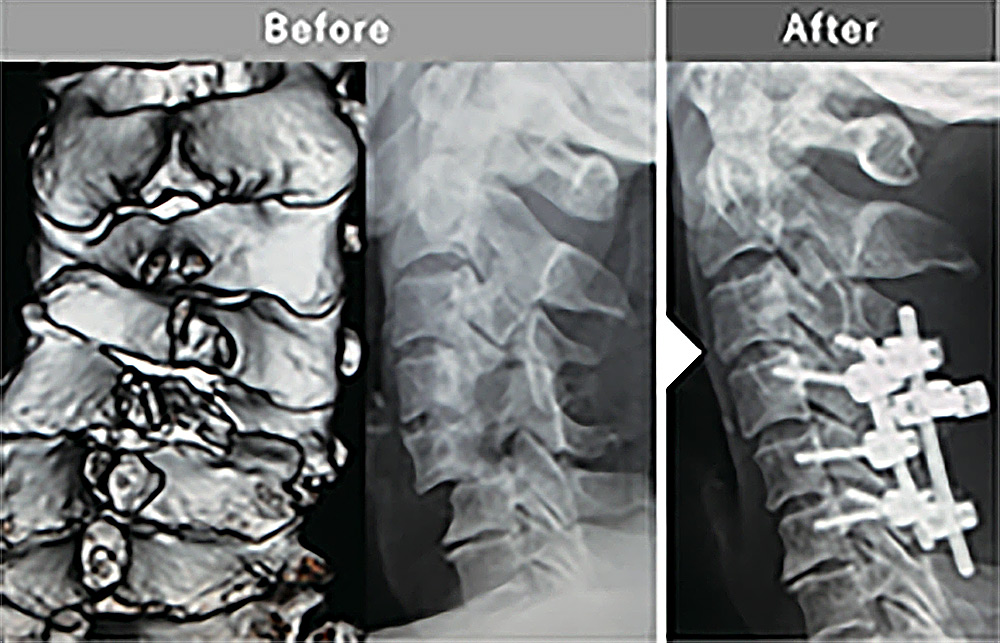

整復固定術

複雑な脊椎外傷に対する整復固定術

医療の現場は常に緊張感がつきものですが、従来の外科手術ではリスクが大きく出来なかった症例も正確性は向上し、安全に手術ができる領域は広がりました。また、除圧範囲の設定が細かく行えることで、これまで判断が難しかった切除できる骨の範囲も明確に判断できます。そのほか、脱臼した時の整復状態の確認などにも幅広く応用でき役に立っています。